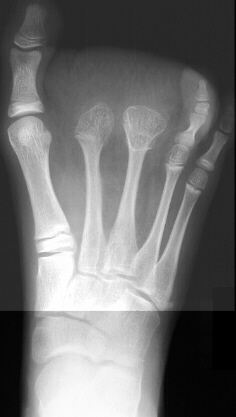

Bridget is a 10 and a half yr. old white female with macrodactyly of the right foot. In may of 1985 she had an amputation of the 2nd and 3rd toes at the level of the mid diaphysis proximal phalanx and extensor tendon release of the 2nd and 3rd toes with excision of abnormal fibrofatty tissue of right foot, and most recently in 1990 she underwent partial amputation of the right 2nd and 3rd metatarsals . She has been doing well, participating in all sports. She has noted that there has been some difficulty in finding shoes that fits but does not complain of any pain.

She has an increased soft tissue bulk in the forefoot. The skin is otherwise in good condition, no areas of breakdown. It is non tender and incisions are all well healed. X-rays reveal the metatarsal and phalangeal physes are still open. Family History is negative.